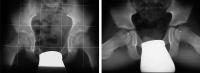

Abbildung 1: Linkes Hüftgelenk. St. p. eitriger Coxitis: Femurkopf und Schenkelhals sind "weggeschmolzen", das Femur stützt sich nur an der Darmbeinschaufel ab.